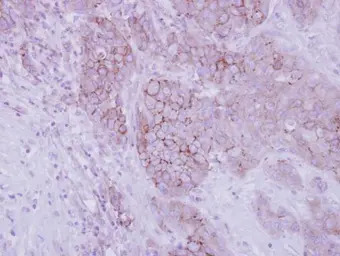

Opsin 3 antibody [N1], N-term detects Opsin 3 protein expression by immunohistochemical analysis.

Immunohistochemical analysis of paraffin-embedded human breast cancer, using Opsin 3(GTX108155) antibody at 1:250 dilution.

Antigen Retrieval: Trilogy™ (EDTA based, pH 8.0) buffer, 15min